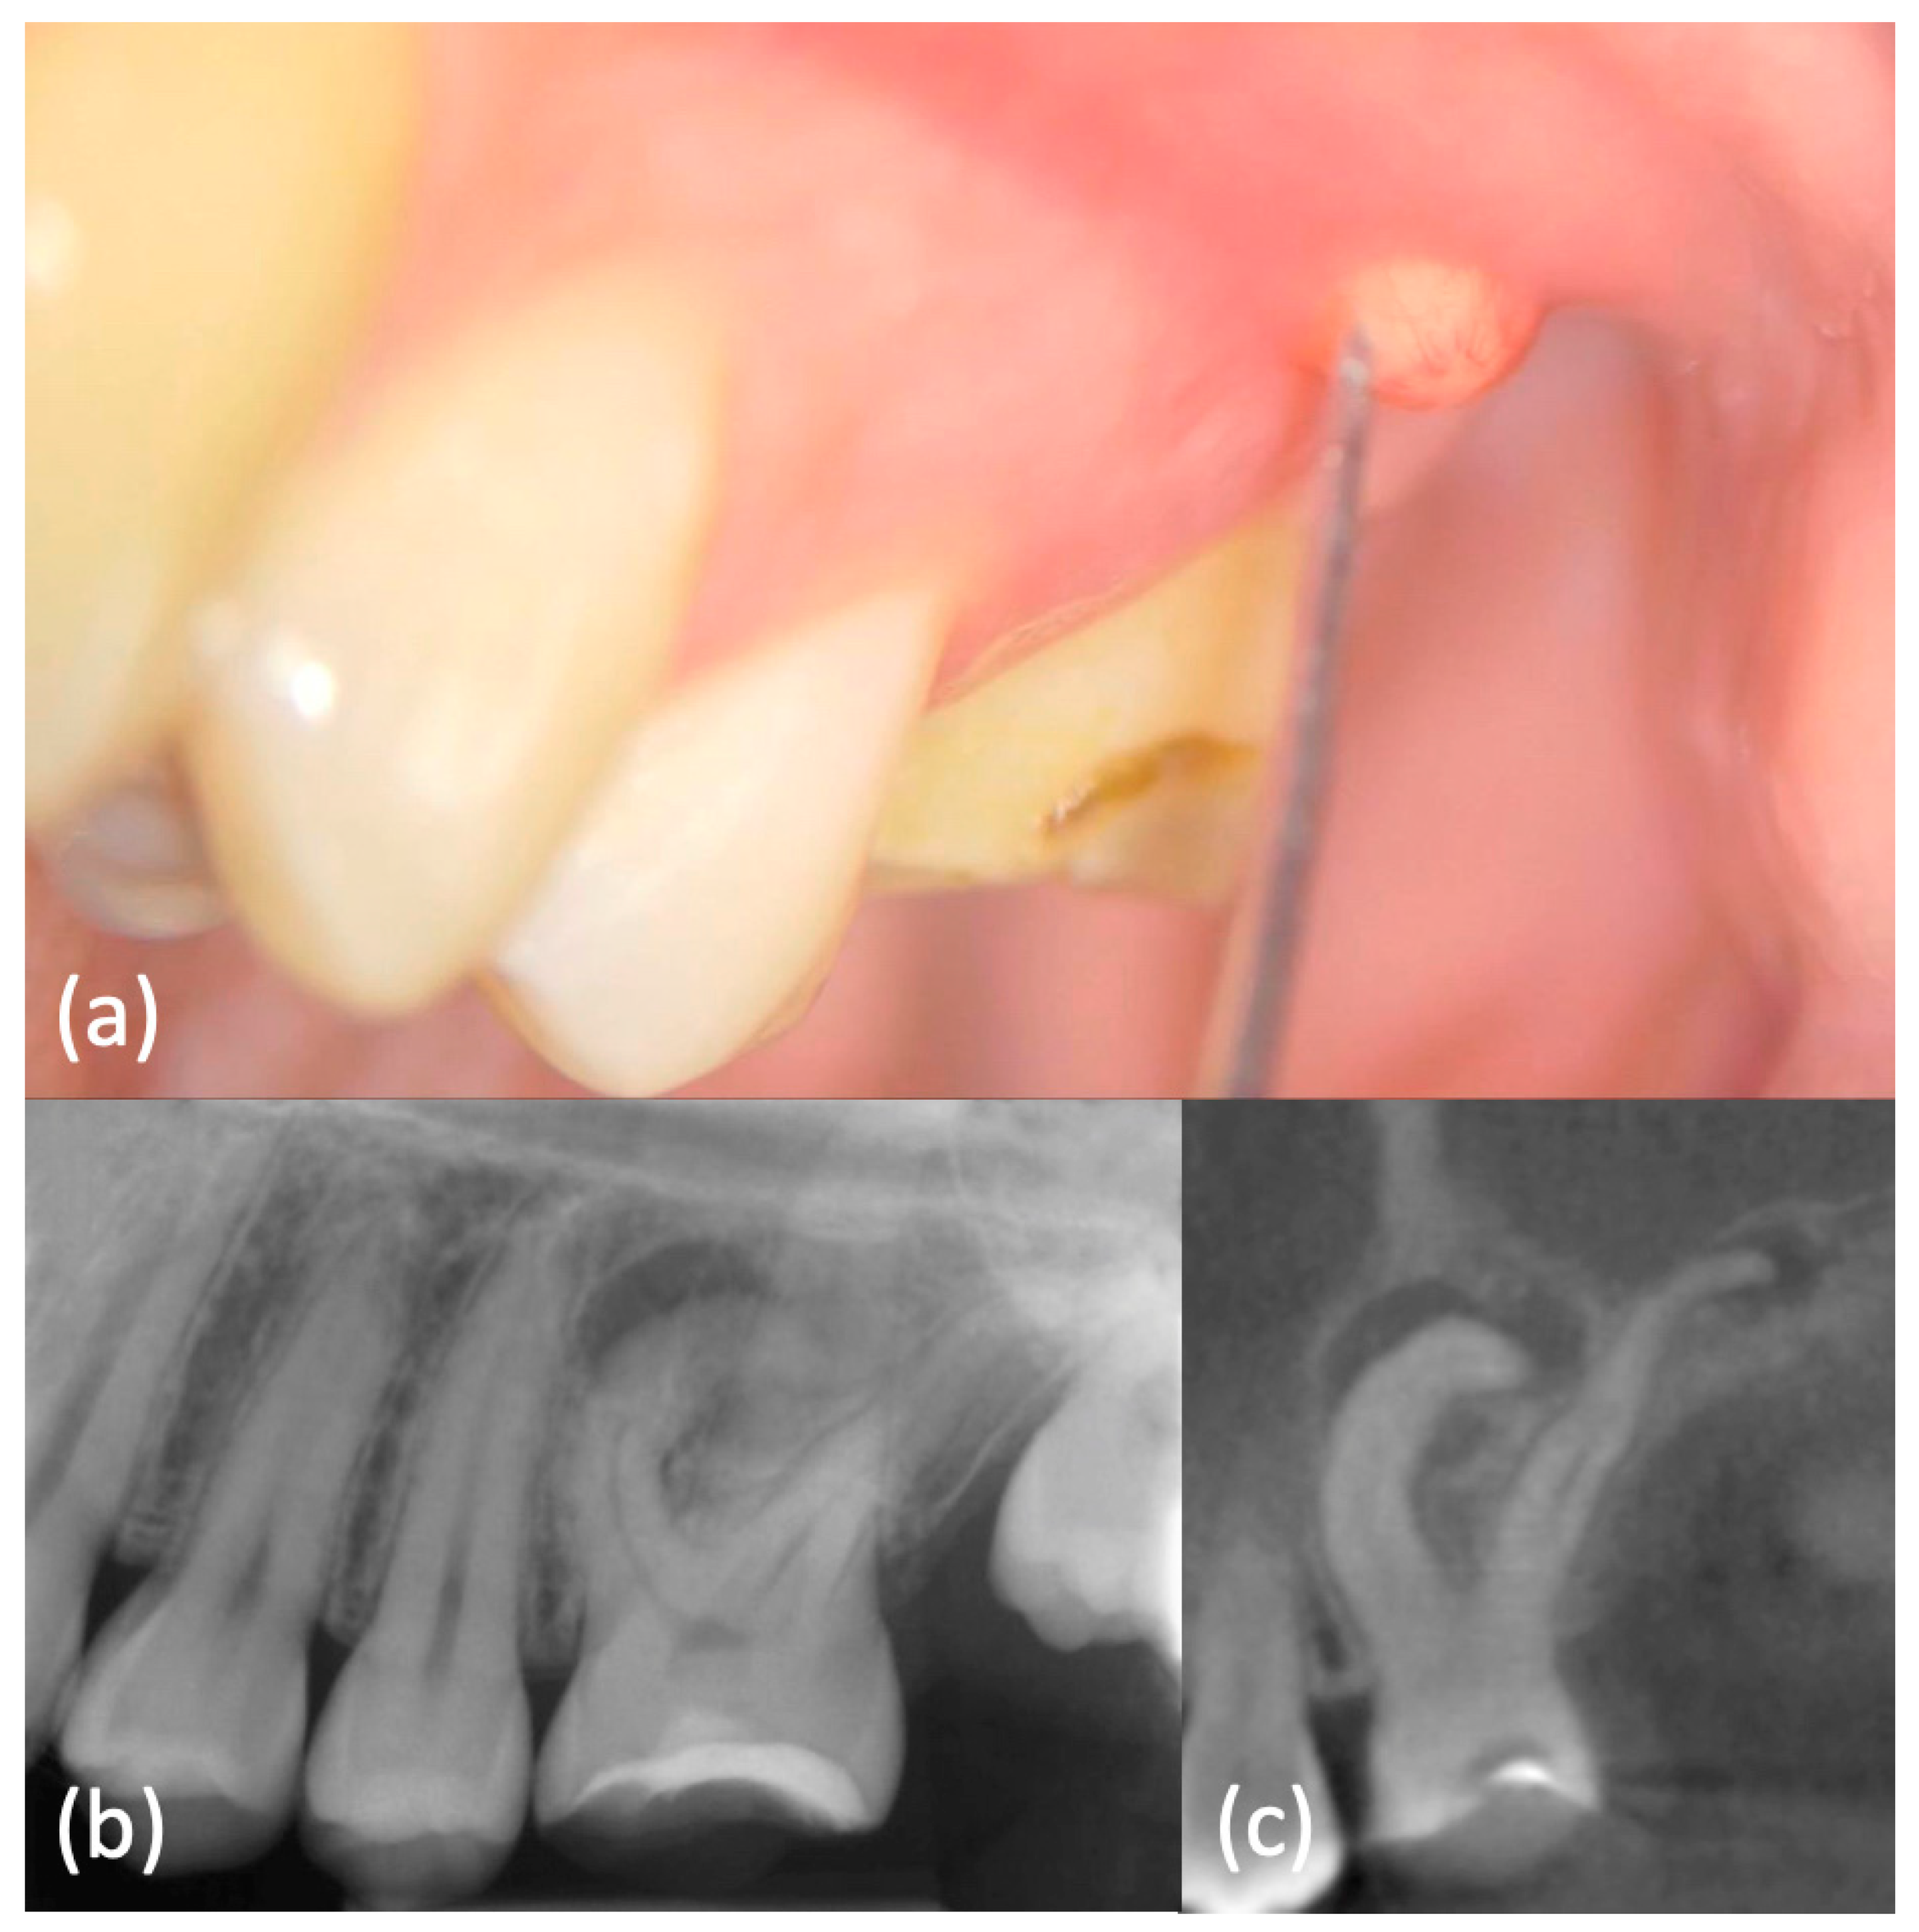

History and physical examination: A 16-year-old otherwise healthy female was seen in emergency because of pain in her right maxillary region. An extraoral examination did not reveal swelling or other abnormalities. An intraoral examination showed immediately the presence of a lump on the buccal aspect of the tooth 26, which appeared not to be completely erupted and with a typical aspect of dilacerated root morphology on 2D radiographic imaging. A carious lesion was present on the same tooth and element 27 was not erupted (Figure 6a–Movie 6).

Figure 6.

(a) Intraoral examination showed a lump on buccal side of element 2.6, which appeared not to be completely erupted and with a carious lesion. Element 2.7 was clinically absent. (b) Periapical X-ray showed dilacerated roots of element 2.6, with a periapical lesion on the mesial-buccal one. Element 2.7 was not erupted, but present. (c) CBCT confirmed these findings and highlighted a periapical lesion also on the other roots.

Imaging examination and diagnosis: A pre-operative periapical image (Figure 6b) was carried out by long-cone paralleling technique (CS 2200, Carestream Dental, Rochester, NY, USA). It confirmed the presence of dilacerated mesio- and disto-buccal roots and the diagnosis of chronic periapical periodontitis. The tooth 27 was not erupted because of aberrant root morphology of the mesial element.

This radiography had an important role in the preliminary assessment of the irregular morphology of the root canal system, but it provided only a 2D-representation of the complex anatomy. Therefore, a small-FOV CBCT (Figure 6c–Movie 7) was indicated based on the current ESE guidelines. It provided a 3D image of the dilacerated tooth and its surrounding tissues and helped to determine the exact position and angulation of the dilaceration abnormality, which was found to also affect the palatal root. Apical radiolucencies were detected within the woven bone surrounding the apices of all roots. These diagnostic findings could be obtained only with CBCT imaging. An orthograde primary root canal treatment was recommended to the patient.